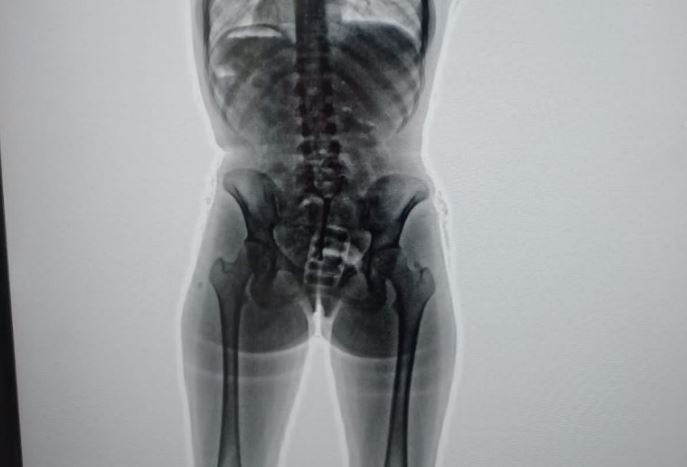

Sin embargo, sus dudas persistían, por lo cual, con la colaboración de la Policía de Seguridad Aeroportuaria (PSA), procedieron a realizarle un body scan que arrojó imágenes comprometedoras.

En ese sentido, se advertía la presencia de cuerpos extraños en su organismo. Concretamente, había introducido en su vagina un profiláctico con 11 cápsulas de cocaína, de aproximadamente 10 gramos cada una.

En ese momento, la PSA y la Aduana dieron aviso a la Justicia y fue así que intervino el Juzgado Nacional en lo Penal Económico número 6, a cargo de Marcelo Aguinsky, que ordenó el traslado de la mujer al Hospital Eurnekian, en Ezeiza. Allí, bajo custodia de la PSA, estuvo incomunicada mientras evacuaba los cuerpos extraños advertidos en las imágenes del escáner. Estos resultaron ser 67 capsulas más, dando un total de 78, con 742 gramos de cocaína.